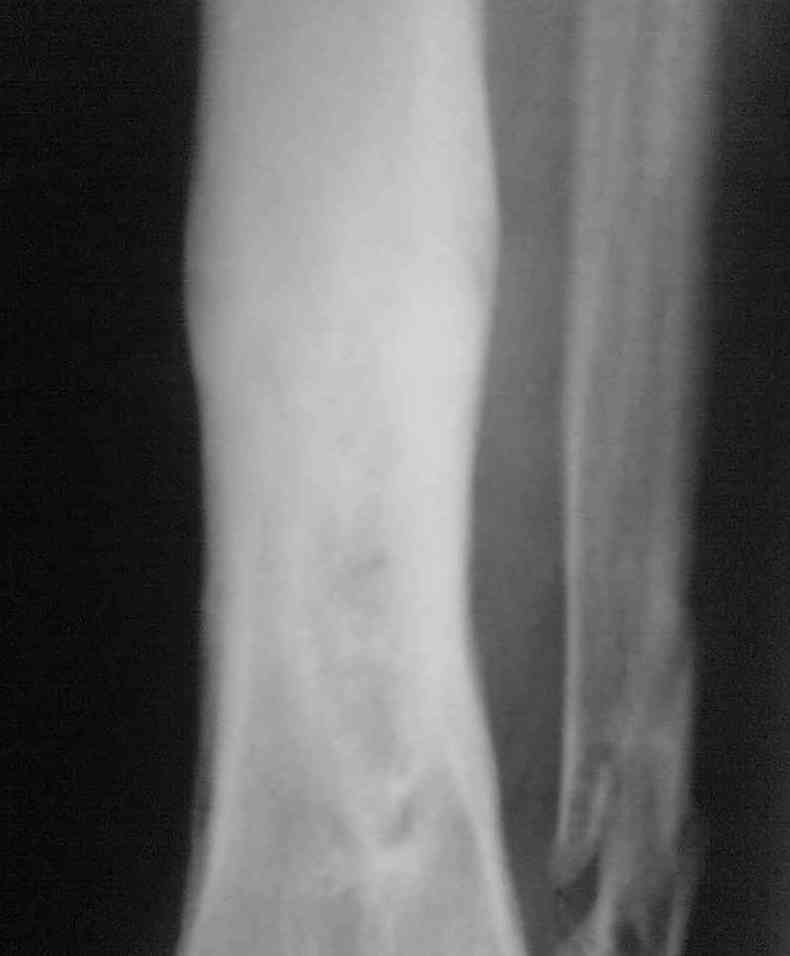

Выкладываю снимки в хронологическом порядке. Снмки все какие есть у больного.